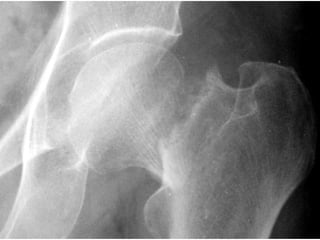

Measure the size of the head

Neck Cut

Proximal Fixation Tips & Tricks Pre-operative assessment of the Canal. Proper neck cut. Avoid comminuting Calcar Femoris. Save at least 1cm of neck at Calcar Insert canal finder from Piriformis Fossa In wider canal, avoid use of rasp.